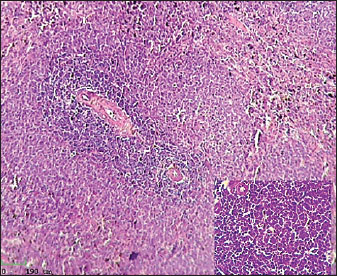

Histological examination of the splenic tissue of rats treated with L-arginine showed notable pathological alterations. These included: Congestion of blood vessels within both the red and white pulp and lymphoid hyperplasia in the white pulp, indicating increased proliferation of lymphoid cells, suggestive of immune stimulation or chronic inflammation (Fig. 4). In contrast, the spleen from control male rats exhibited normal histological architecture. The white pulp and red pulp regions were clearly distinguishable. Central arteries and blood vessels appeared unremarkable, and no signs of congestion, inflammation, or hyperplasia were observed. The lymphoid follicles within the white pulp were of normal size and density (Fig. 3)

Fig. 3. Histological section of male rat spleen of control group, stained with Hematoxylin and Eosin (H&E), showing villus structure at 10x magnification using light microscopy.

Fig. 4. Histological section of male rat spleen treated with L-arginine, stained with Hematoxylin and Eosin (H&E), showing villus structure at 10x magnification using light microscopy.

Lymphoid hyperplasia of the spleen is when there are more lymphocytes than usual. It usually happens because of an inflammatory or immune response. This finding usually means that the immune system is working harder or longer in the spleen, which shows that the immune system is still controlling the body as a whole. This kind of hypertrophy is a sign of an active immune system or long-term inflammation (Hobbie et al., 2024).